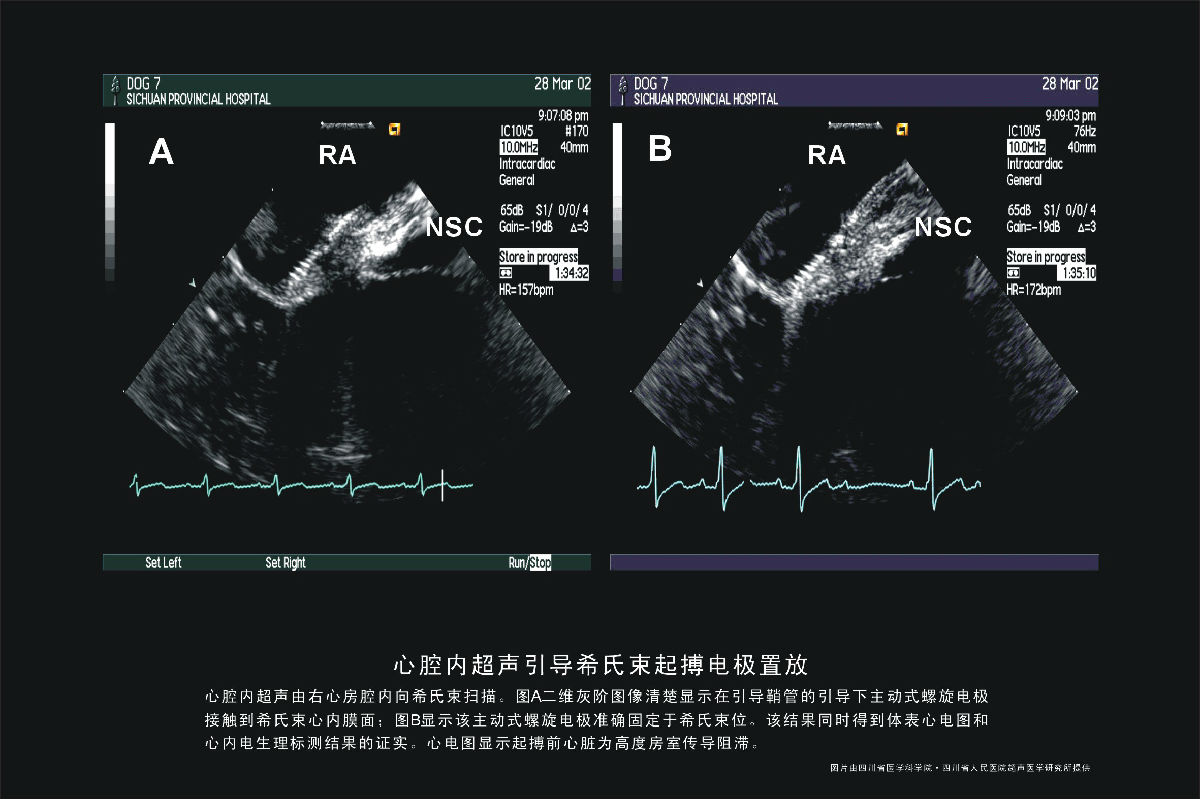

希氏束起搏电极置放